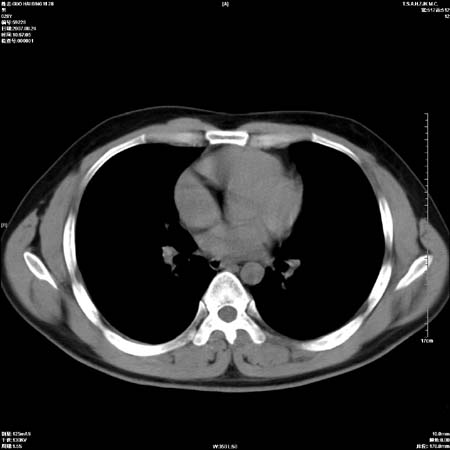

男性,28岁,体检发现左肺病变,患者只有背部隐痛感,哀哉,真不忍心下诊断啊。

左肺门区软组织肿块,左肺上叶支气管开口消失,纵隔内见肿大淋巴结,考虑左中心型肺部,可以做纤支镜取病理确认.

左肺肺门区肿块影,分叶明显,左肺上叶支气管开口受压,纵隔内见肿大淋巴结,考虑左中心型肺癌。